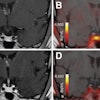

Unfortunately, there are obstacles to overcome. For example, cancers evolve in time to become harder targets to treat. So how can medical physics help? "We need to capture the whole disease and the evolution of disease, using multimodality imaging techniques such as optical and molecular imaging," Jeraj explained. In radiation therapy, such a shift from anatomical imaging and population-based treatment, to molecular imaging, patient-specific therapies and nonuniform dose delivery is the foundation of "biologically conformal radiotherapy."

Jeraj noted that medical physics must also strive to treat more advanced cancers. He described a case in which PET imaging of a patient with advanced metastatic prostate cancer revealed multiple, extremely heterogeneous lesion responses: responding, nonresponding, stable, emerging, and disappearing. "How can you treat this patient with one modality? You can't," he said. But such information would possibly enable selective localized targeting (by radiotherapy, for example) of selective nondrug-responsive lesions. "Radiotherapy can be exploited to big advantage of patients with highly advanced disease."

Looking forward, Parodi suggests that we may now be entering the era of biological guidance. "The next dimension to explore for ART is biological guidance," she told the delegates. One example is the use of PET for stratification, therapy personalization, and response assessment. Including oxygen-enhancement ratio in ion beam planning, meanwhile, could enable dose or cell killing painting of inhomogeneous tumors.